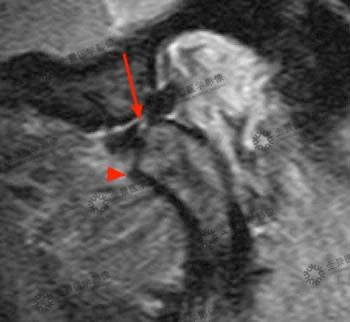

不可复性关节盘前移